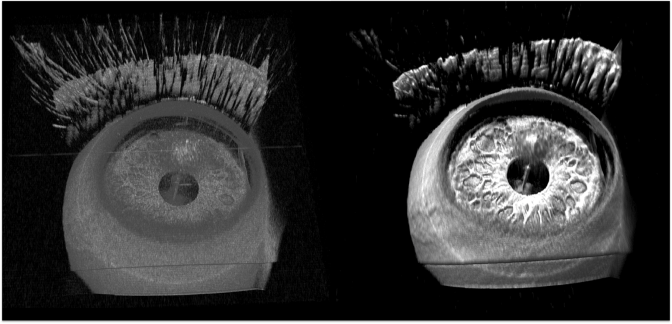

The fourth finalist group is Joseph Izatt and his team at Duke University for their work in using GPU-accelerated, real-time stereoscopic 3D data for eye surgery. A single Titan GPU takes a stream of raw “optical coherence tomography” (OCT) data, processes it, and renders 3D volumetric images.

Comparison of conventional rendering (left) and enhanced ray casting with denoising (right) of the anterior segment

These images, at a resolution of a few micrometers, are projected into microscope eyepieces. With Nvidia 3D Vision-ready monitors and 3D glasses, live stereoscopic data can be viewed by both a surgeon using the microscope and a group observing the operation as it occurs. The blog post is titled “How GPUs Help Eye Surgeons See 20/20 in the Operating Room.”